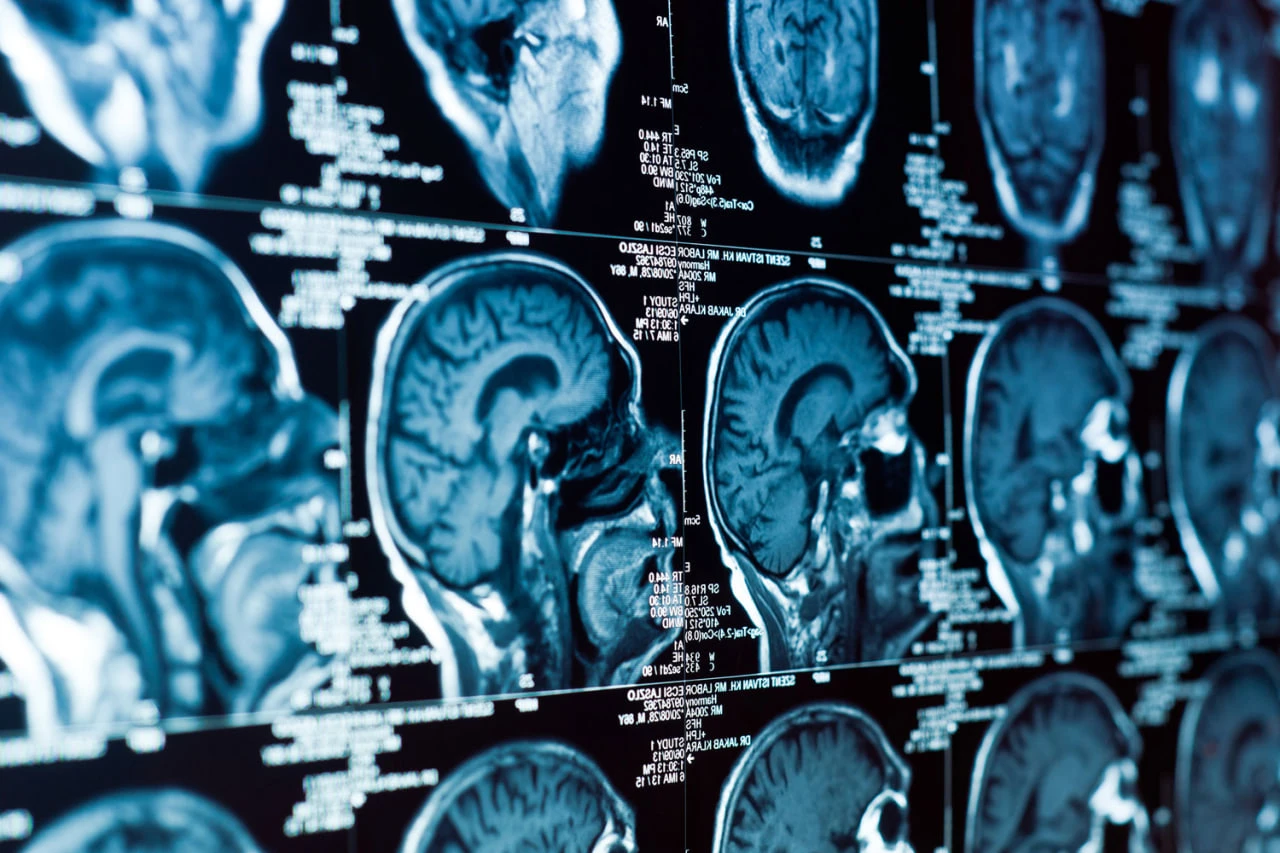

اكتشف العلماء كيف يتغير شكل الدماغ في حالة الخرف

قد تكون التغيرات في شكل الدماغ مع تقدم العمر مرتبطة بخطر الإصابة بالخلل. تم التوصل إلى هذا الاستنتاج من قبل جامعة كاليفورنيا (UC IRVINE) وجامعة لا لاغونا، جامعة لاغونا، إسبانيا. تم نشر أعمالهم في مجلة Nature Communications (Natcom).

وقد أتاح أكثر من 2600 تحليل لمسح الدماغ بالرنين المغناطيسي للعلماء متابعة كيفية تحول الدماغ مع تقدم العمر وكيفية ارتباطه بنتائج الاختبارات المعرفية. اتضح أن التغيرات في شكل الدماغ تحدث بشكل غير متساو. يتم ضغط بعض الأجزاء، بينما يتسع البعض الآخر، وتكون هذه التشوهات أكثر وضوحًا عند الأشخاص الذين يعانون من علامات السقوط المعرفي.

يوضح نيلز يانسن، طبيب الأعصاب بجامعة لا لاجونا، نيلز يانسن: "لقد وجدنا أن الطريقة ثلاثية الأبعاد للدماغ تتغير مع تقدم العمر، وتتأثر هذه التغييرات بشدة بالذاكرة والحكم".

وقد أولى الباحثون اهتمامًا خاصًا بالقشرة الأنليكينية، وهي جزء من الدماغ، الذي يلعب دورًا مهمًا في تسوية الذاكرة. يعد التقشير الشفاف أحد الأجزاء الأولى من مرض الزهايمر. يعتقد العلماء أن تغيرات عمر الدماغ يمكن أن تضغط على هذا الشخص الضعيف، مما يخلق الظروف لتراكم البروتينات السامة وتلفها.

وقال مايكل جاسان، طبيب الأعصاب بجامعة كاليفورنيا في إيرفاين: "إذا تشوه الدماغ المسن بحيث يتم "ضغط" اللحاء المغطى، فإن هذا يمكن أن يفسر سبب تحوله إلى مركز لمرض الزهايمر".

يمكن لهذه الدراسة أن تغير النهج المتبع في تشخيص الأمراض التنكسية العصبية. ويؤكد المؤلفون أن فهم هندسة الدماغ يمكن أن يلعب دورًا مهمًا في الاكتشاف المبكر للخلل، وليس فقط لتقييم عواقبه.